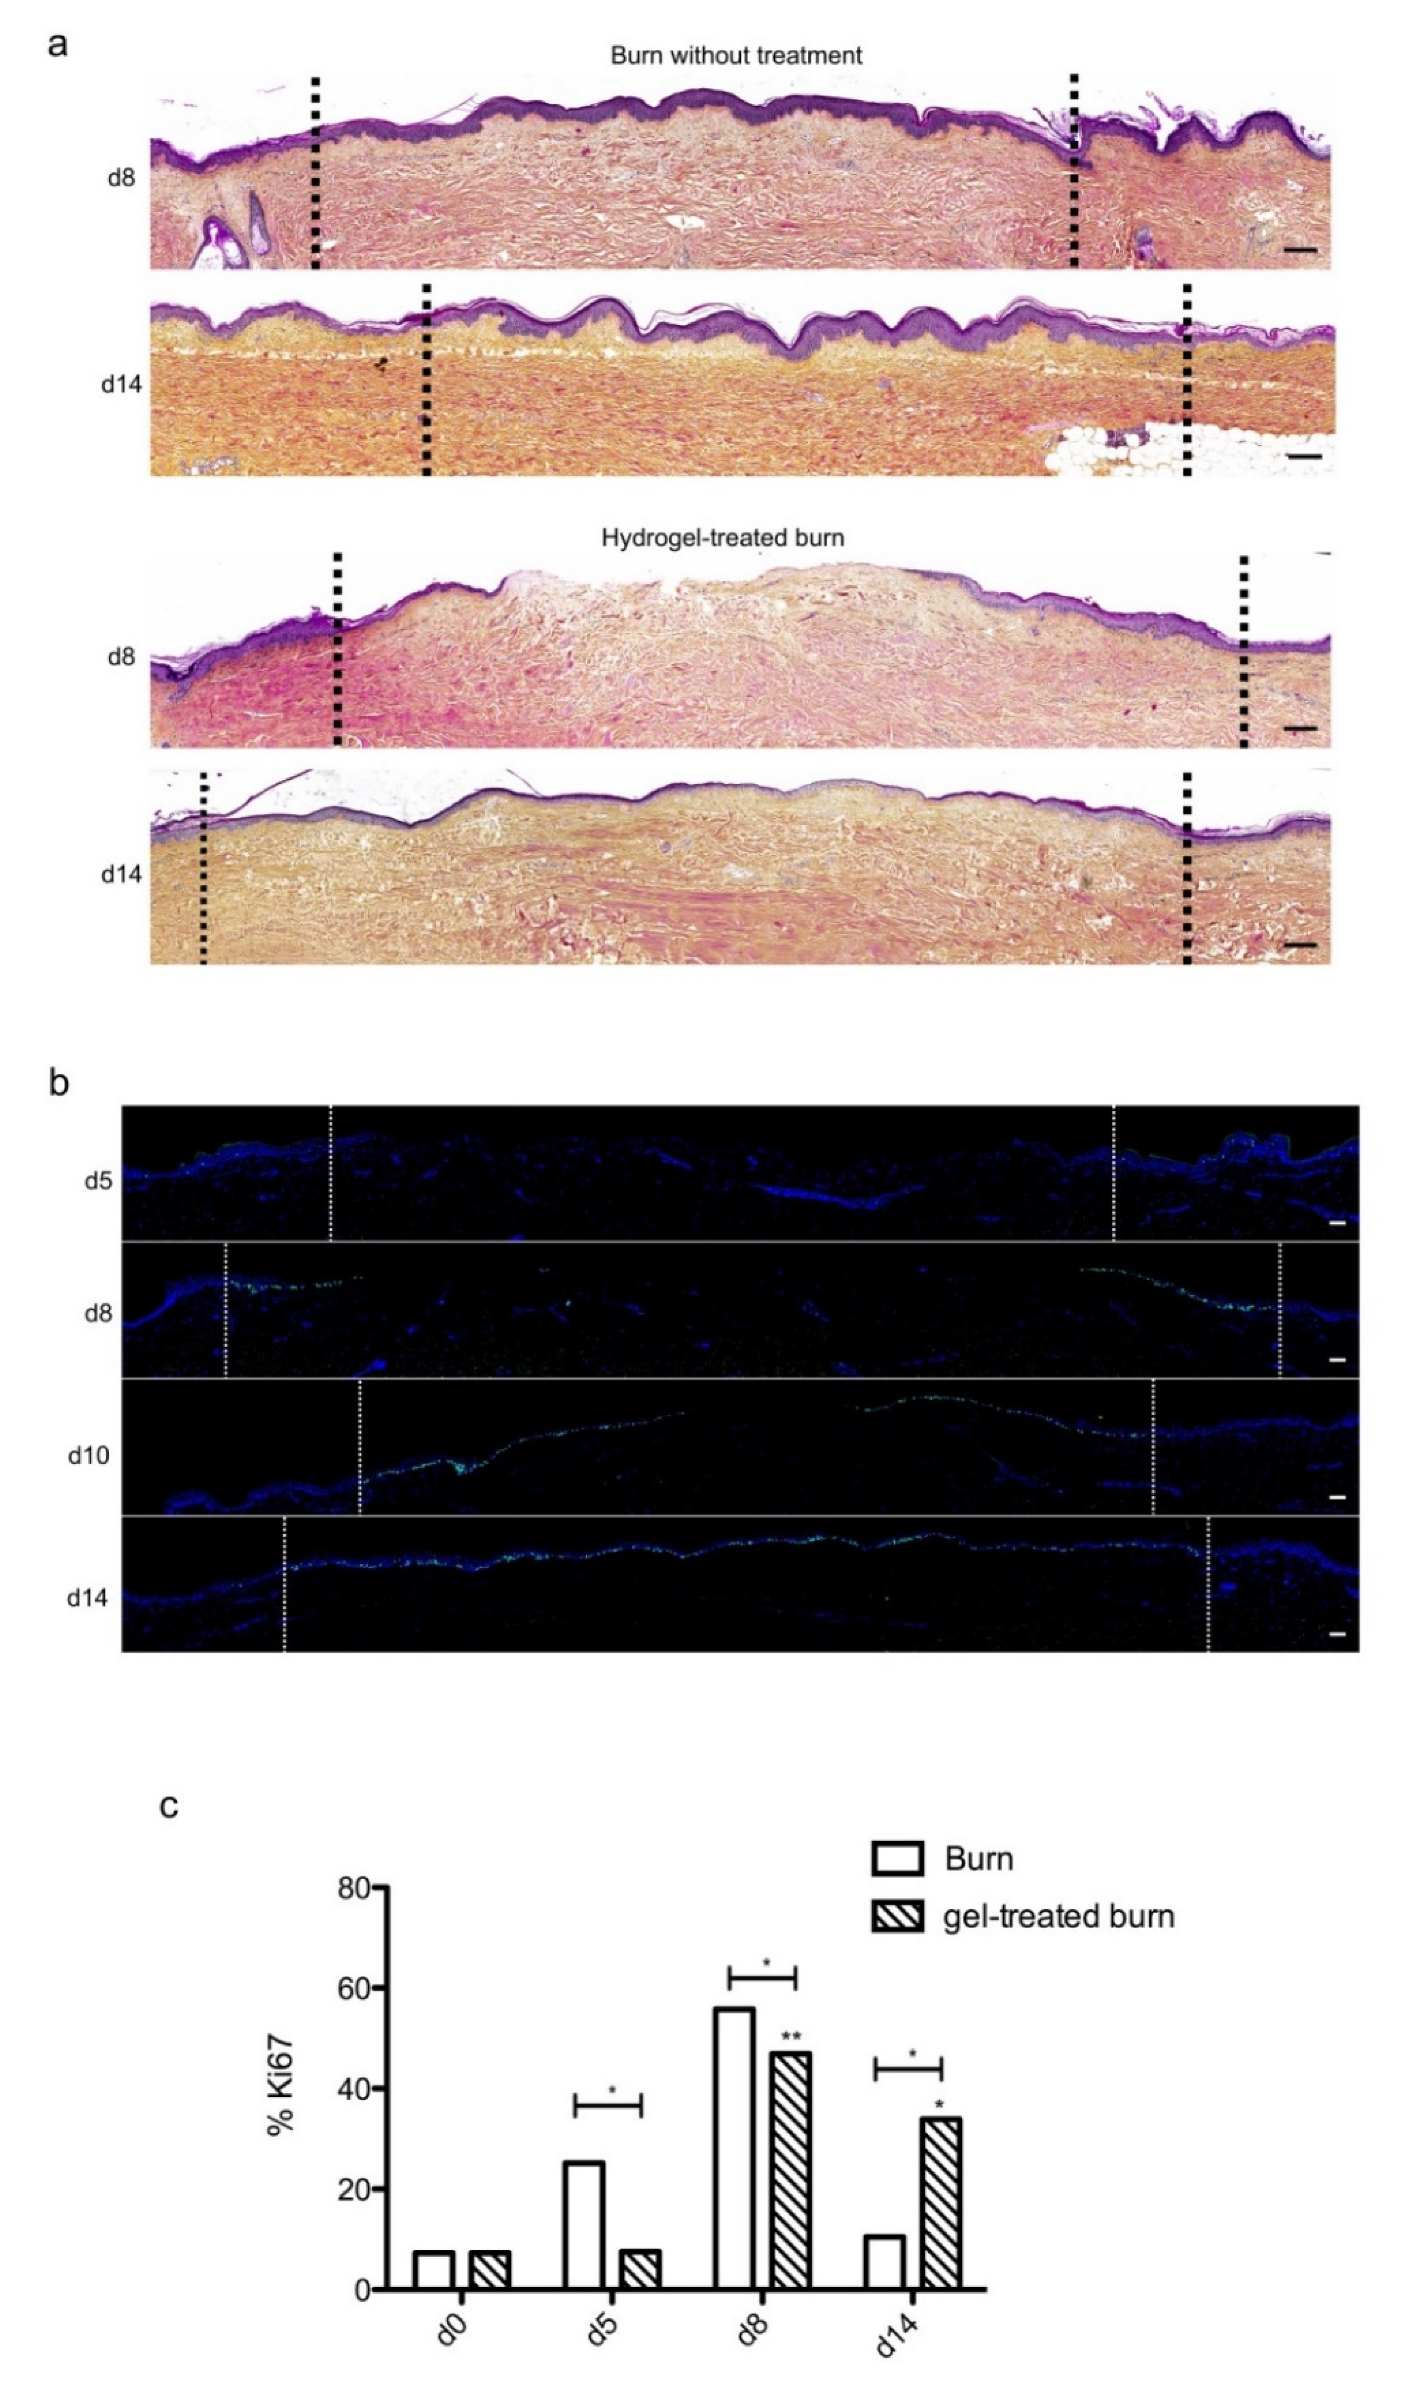

2.6. The Topical Application of a Poloxamer Hydrogel Delays but Does Not Prevent Tissue Repair in Human Skin Explants Subjected to Experimental Deep Second-Degree Burn Injury